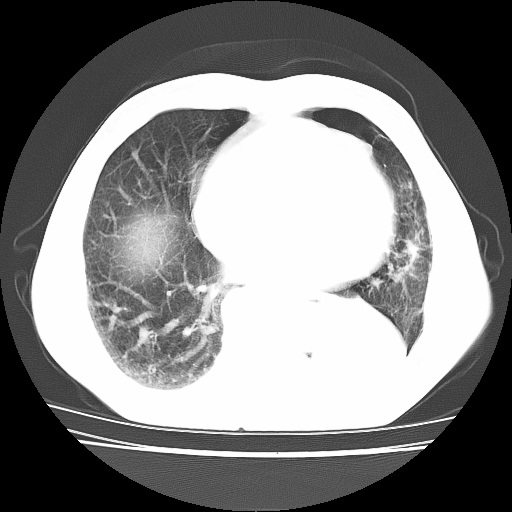

男,71岁,咳嗽,气喘10年,再发并咯血.胸片见气胸

考虑  左肺中心型肺癌伴阻塞性肺炎,肺不张,纵膈淋巴结肿大。慢支炎,肺气肿,左侧气胸肺压缩5%

左侧中央型肺癌伴纵膈淋巴结转移。

左肺中心型肺癌伴阻塞性肺炎,肺不张,纵膈淋巴结肿大

1)考虑左肺中心型肺癌伴阻塞性肺炎、左肺下叶肺不张、左侧肺气肿,纵膈淋巴结转移。2)左侧气胸(肺组织压缩约5%)。

左肺中心型肺癌伴阻塞性肺不张、肺气肿 。

1)考虑左肺中心型肺癌伴阻塞性肺炎、左肺下叶肺不张、左侧肺气肿,纵膈淋巴结转移。2)左侧气胸。